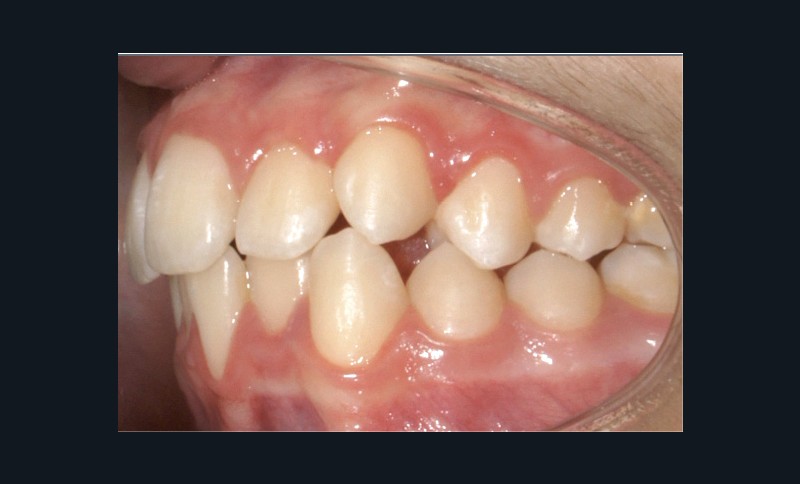

Examen endo-buccal (fig. 2a-e)

Au niveau des relations occlusales, on observe une Classe I molaire associée à une Classe II canine de 2 mm à droite ainsi qu’une Classe II molaire de 1 mm et une Classe II canine de 3 mm à gauche. Le surplomb est normal.